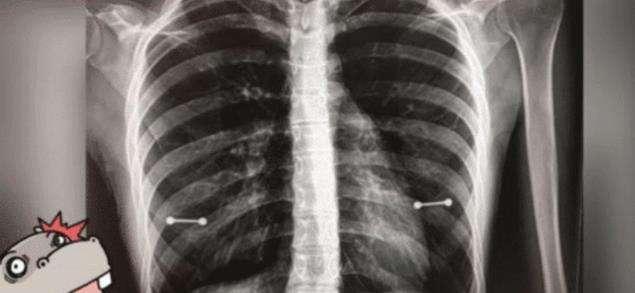

不知道大家有没有去拍过x光片 , 在拍x光片的时候 , 医生都会让病人去除身上的金属物品 , 以免影响拍在拍x光片的时候影响结果 。 前段时间 , 国外有位女子去拍前去拍x光片 , 但是最后的结果中却多出了两条棒棒!女孩的母亲非常的紧张 , 因为她很奇怪自己女儿身上怎么会有这种东西 。 但医生却笑着解释说:这是女孩儿上了乳环 , 妈妈听后非常的震惊 , 当时脸色都变了 , 没想到女儿表面上乖巧 , 私下竟这么叛逆 , 所以母亲决定回家后要和女儿好好交流一番 。